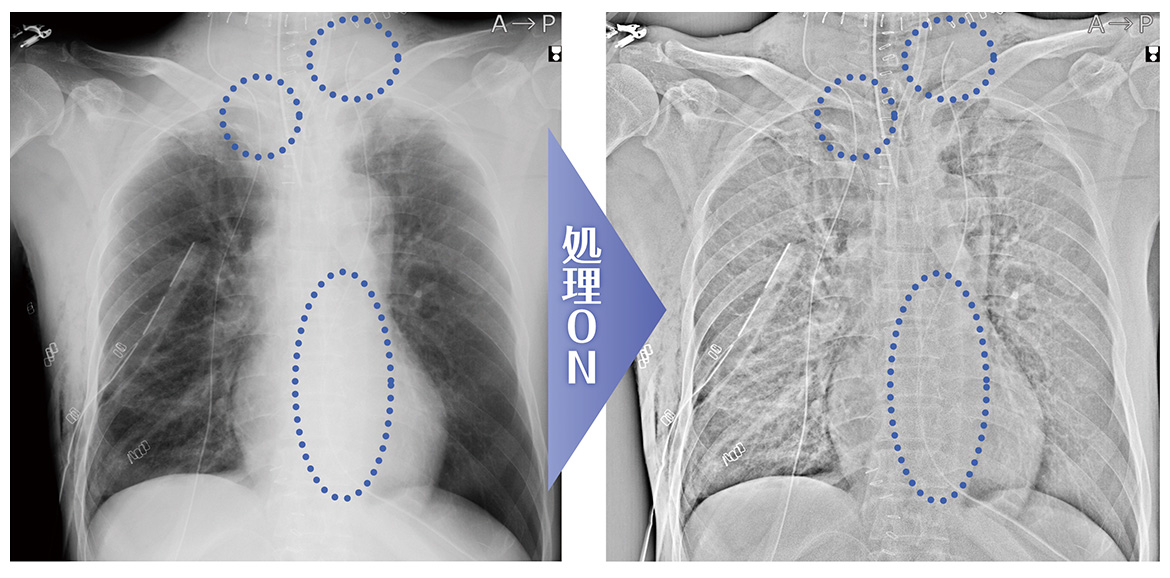

カテ先・ガーゼ強調処理を搭載 ※

ポータブル撮影の目的は、経過観察だけではなく、術後の残存物確認(ガーゼカウント)や、カテーテルや挿管チューブのルート確認等も挙げられます。CS-7 Portableには、そのための専用処理を搭載しました。カテーテルやガーゼなどの確認をしやすくし、即時画像確認のメリットを最大限に活かすことができます。

<対象部位>

胸部正面/胸部側面/腹部正面/腹部側面/頭部正面/頭部側面/小児胸部正面/小児胸部側面/乳幼児胸腹部/新生児胸腹部/聴器/頸部/腰椎側面/胆道造影/手指骨/足根骨/足趾